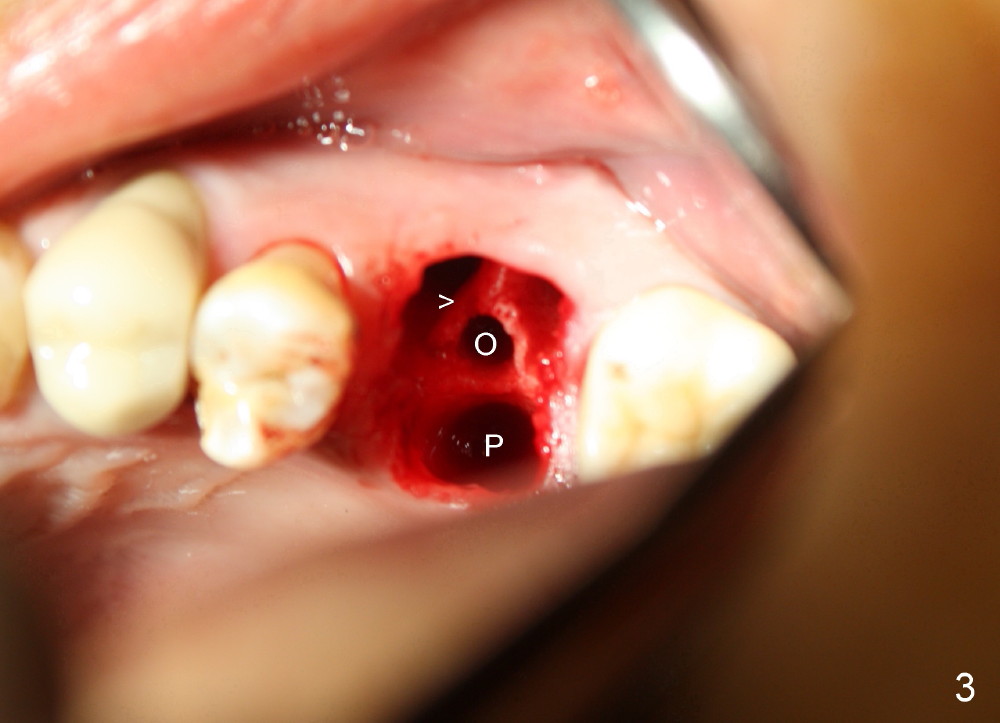

The upper left 1st molar is extracted with sectioning. The septum is large. A surgical fissure bur is used to initiate an osteotomy in the middle of the septum (Fig.1 <; P: palatal socket, MB: mesiobuccal socket), followed by tapping with resistance a 2 mm osteotome ~ 8 mm into the septum. It is tougher to drive 3 mm osteotomy. A 2.5 mm reamer is used to enlarge the osteotomy at 50 RPM at the same depth. Then it is relatively easy to tap 3 and 4 mm osteotomes at ~ 8 mm into the septum. A 4.5x17 mm tap is inserted 8 mm deep with binding to the septum. PA is taken (Fig.2). It appears that the sinus floor (black >) has been penetrated, but the osteotomy has not reached the apex (white >) of the palatal (P) socket. Then the tap is advanced ~ another 3 mm. When the tap is removed, the osteotomy (Fig.3 O) is slightly toward the buccal aspect of the extraction socket, but it has intact wall, including the mesiobuccal (>). The apex of the ostoetomy has no bone, but there is no air leakage. The next tap, 5x17 mm, is inserted shallower (~ 8 mm in the septum; to reduce potential trauma) with stability. However, 6x17 mm tap at the same depth does not obtain stability, since the osteotomy deviates severely mesiobuccally (Fig.4 arrow) with breakdown of the mesiobuccal wall. So the osteotomy has to be deeper in order to achieve stability of 6x17 mm tap (by engaging into more apical bone). A 7x17 mm tap is then intended to be inserted to close the socket as much as possible, but as it is being inserted, the osteotomy is more severely deviated and tilted mesiobuccally with the original mesiobuccal wall further being broken down (not shown). It appears to compromise stability. Mixture of autogenous bone from reamer, allograft and synthetic bone is placed in the mesiobuccal and palatal sockets before placement of the 6x17 mm implant (Fig.5 I). Unfortunately some of graft blocks the apical osteotomy. To clear the blockage, some of previous osteotome and taps are re-inserted. The result is in fact beneficial, as bone graft (G) is pushed upward. Prior to implant placement, nose blowing test does not produce air leakage. More allograft is placed in the coronal portion of the sockets (Fig.6 G); an abutment with precut slots is placed (A) with intention of better holding perio dressing in place after placement of a collagen dressing (Fig.7 M). A temporary crown may be placed when the perio dressing is dislodged. The provisional is to keep the membrane and bone graft in place. The patient returns for follow up 1 week postop. He is symptom free. The abscess appears to be resolving (Fig.8 >); the perio dressing remains in place.